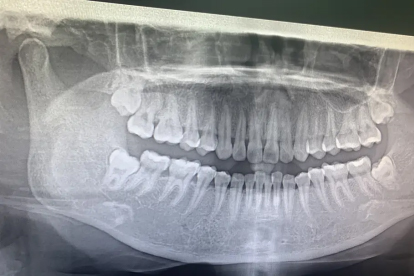

拔完阻生智齿后关节弹响多数会逐渐缓解,少数可能持续存在。阻生智齿拔除可能因手术创伤、张口时间过长等因素导致颞下颌关节暂时性功能紊乱,表现为弹响、疼痛或张口受限。

若弹响持续超过1个月或伴随明显疼痛,可能与颞下颌关节结构损伤有关。长期阻生智齿可能导致关节盘移位,拔牙后咬合改变可能加重关节负荷。此类情况需口腔颌面外科评估,必要时通过咬合板治疗、关节腔冲洗或物理治疗干预。